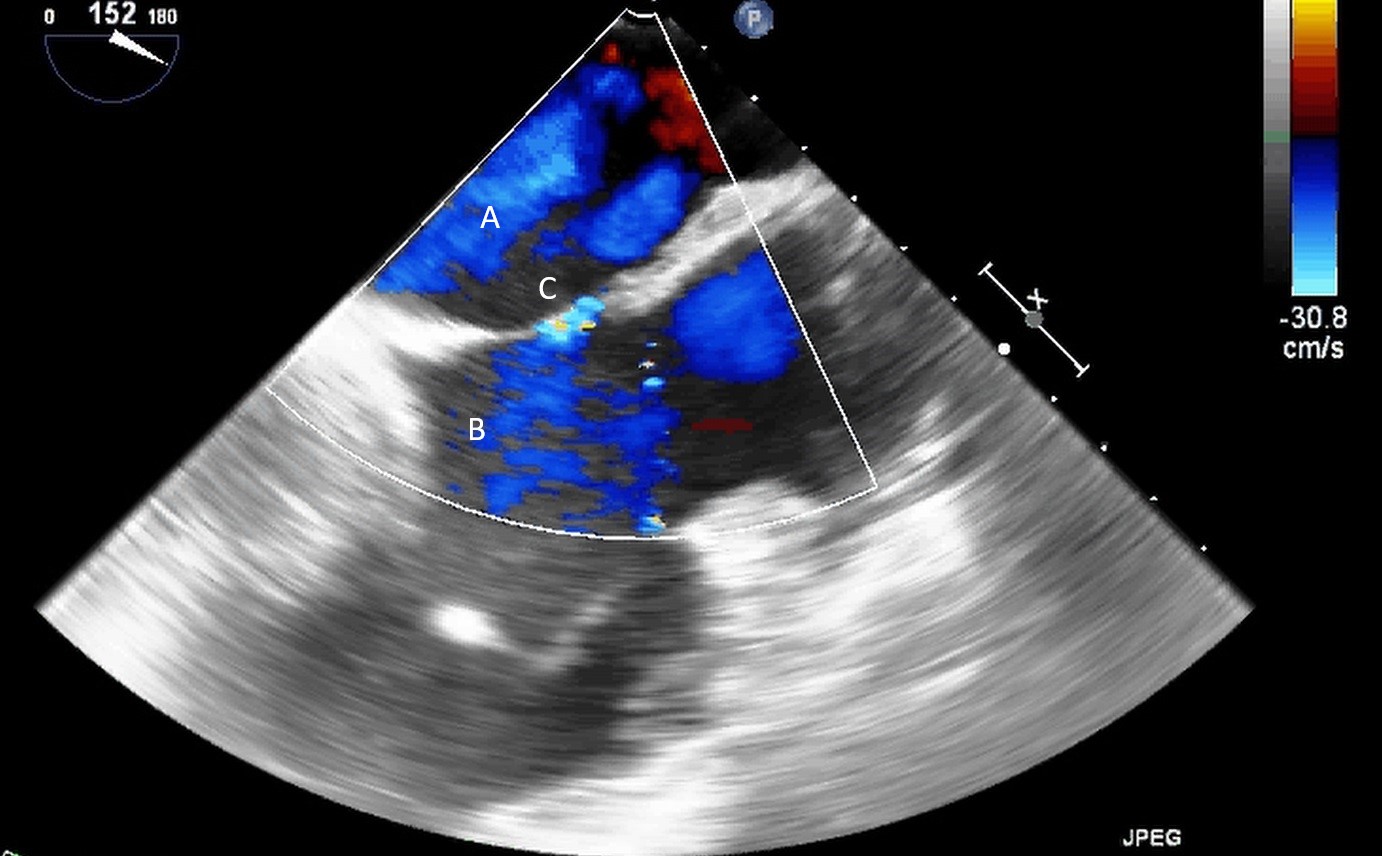

The prevalence of a patent foramen ovale (PFO) in the U.S. population is approximately 25% [54]. Identification of an interatrial shunt is critically important before LVAD implantation (Fig. 18). Due to the risk of hypoxemia and paradoxical embolization in patients with LVAD, any interatrial communication is typically closed at the time of device implantation [55]. Given the potential risks associated with a PFO in the post LVAD patient, agitated saline and color flow imaging by TEE can be helpful in its identification.

Fig. 18.Transesophageal bi-caval view (Pre-LVAD implantation) demonstrating a left-to-right interatrial shunt by color-flow imaging (C). (A) LA. (B) RA.